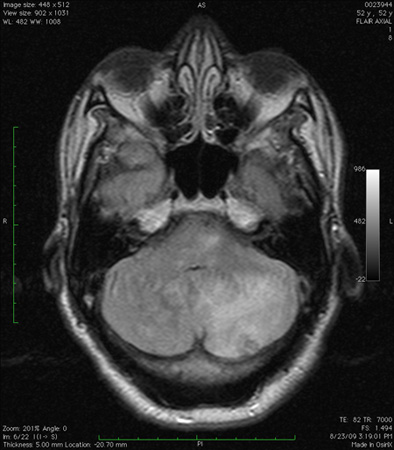

FLAIR მრტ გამოსახულებაზე ჩანს ნათხემის ინფარქტი: შეიმჩნევა მეორადი შეშუპება და მეოთხე პარკუჭის გაფართოება

ექიმი ს.ჰ. საბრამონის კოლექციიდან; გამოყენებულია მფლობელის ნებართვით